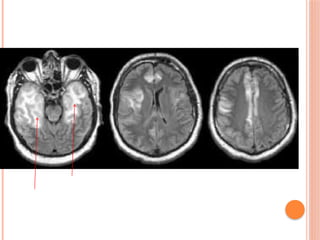

• 11.

 MRI Brainis abnormal specially at day 3 onwards.  Bilateral or unilateral temporal signals are characteristic. Other areas may be affected in other viruses or medical diseases.